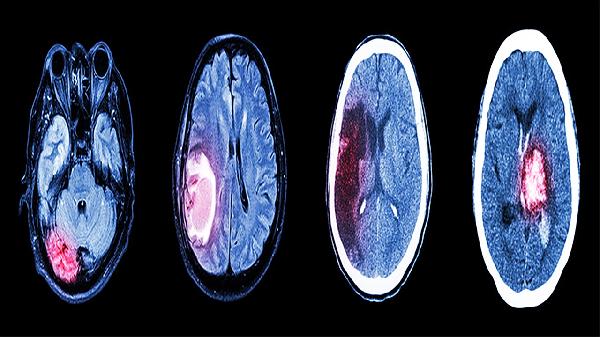

临床上,医生通常会根据受伤后患者的昏迷时间、昏迷评分(如格拉斯哥昏迷评分)、影像学检查结果等进行预后评估。如果早期治疗时能够迅速疏通或减轻颅内高压,同时稳定生命体征,就能为患者恢复争取更大可能性。一些特重型患者通过紧急手术治疗,如去骨瓣减压,结合术后的康复训练和药物干预,也有可能逐步改善意识状态。